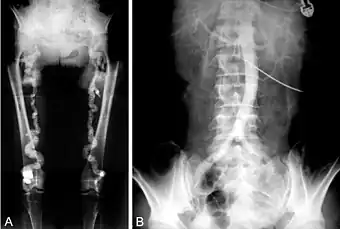

![]() File:PMC3531254 1471-2369-13-139-1.jpg | |